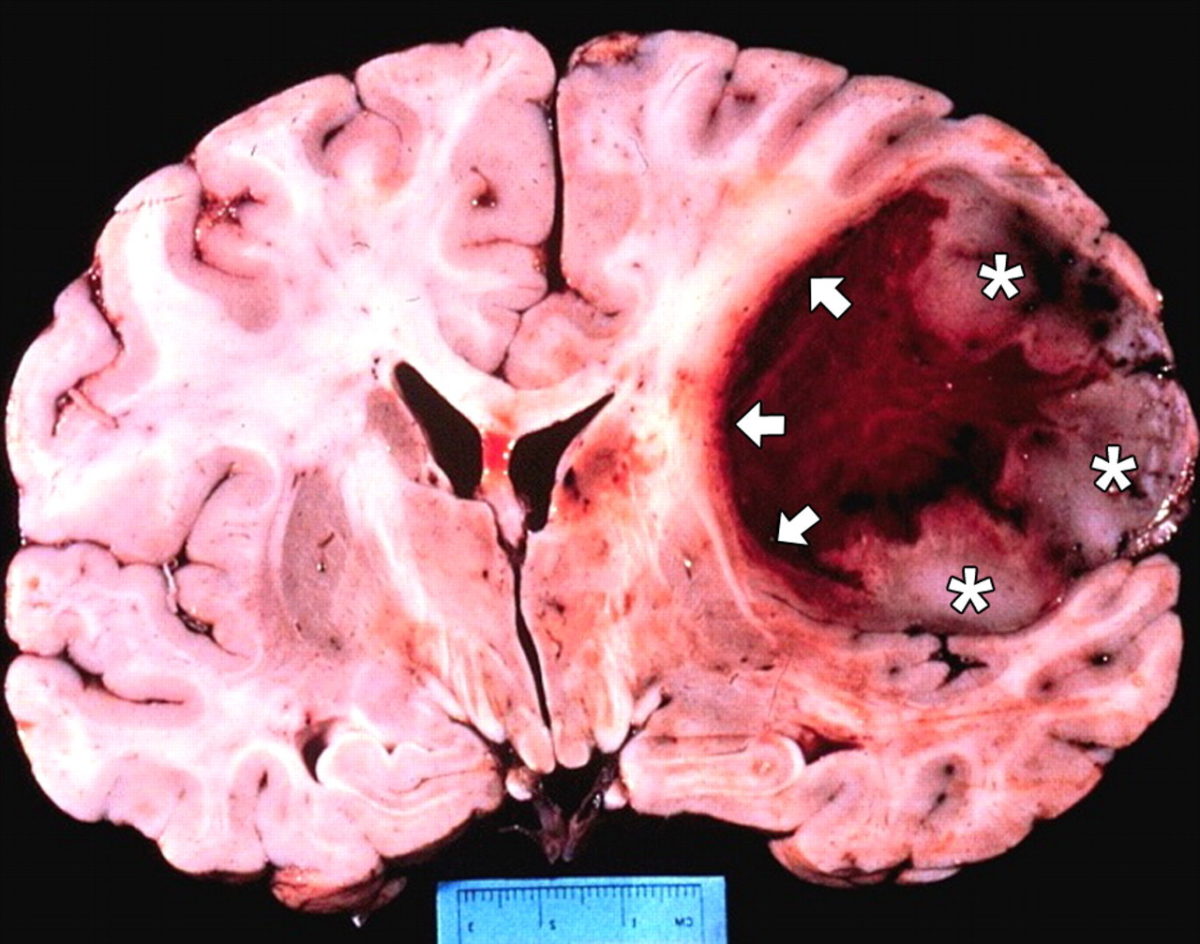

Αξίζει να τονιστεί ότι  το Γλοιοβλάστωμα (γλοίωμα βαθμού IV) είναι η πιο κακοήθης μορφή νεοπλασίας-όγκου που μπορεί να εμφανιστεί στον ανθρώπινο εγκέφαλο.

Πρόκειται για μια διηθητική μορφή καρκίνου χωρίς σαφή όρια από τον υπόλοιπο υγιή εγκέφαλο με ταχύτατο ρυθμό ανάπτυξης .Αποτελεί  το 20% όλων των ενδοκράνιων όγκων σε ενήλικες, ενώ  πολύ σπάνια εμφανίζεται  στην παιδιατρική ηλικία. Σε ετήσια βάση έχουμε 2 με 3 νέα κρούσματα ανά 100.000 άτομα σε Ευρώπη και Βόρειο Αμερική, έχει δε την χειρότερη πρόγνωση από κάθε κακοήθεια του κεντρικού νευρικού συστήματος .